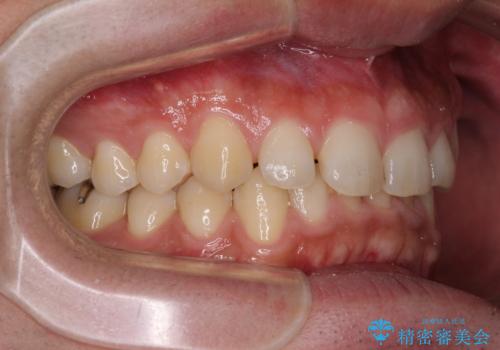

深い咬み合わせと隙間の空いた歯列をワイヤー矯正で改善

- 前歯の隙間と深い咬み合わせを改善したいとのことで来院された患者様です。

奥歯の咬み合わせは理想的な状態であったため、ワイヤー矯正でもインビザラインでも比較的容易に対応可能でした。